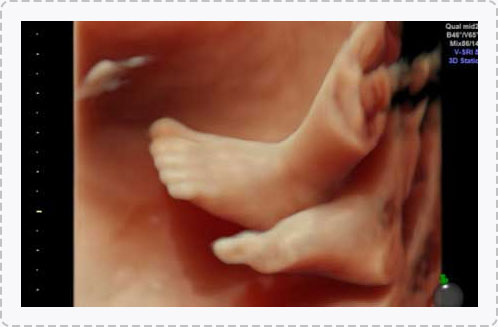

四维彩超能够直观、立体地显示人体器官的三维结构以及动态,实时地观察立体结构,被广泛用于检查胎儿发育状况,立体观察胎儿在子宫内发育情况的同时,还能够清晰显示胎儿在子宫内的动态,让准爸妈们一起观看宝宝在妈妈肚子里的动作、神态,还可将这个过程制作成光碟保存,让宝宝能够拥有完整的0岁相册,留下珍贵的纪念。

四维彩超检查能够多角度观察胎儿在子宫内的发育状况,同时能够为早期诊断胎儿先天性体表畸形、先天性心脏疾病提供准确的科学依据。